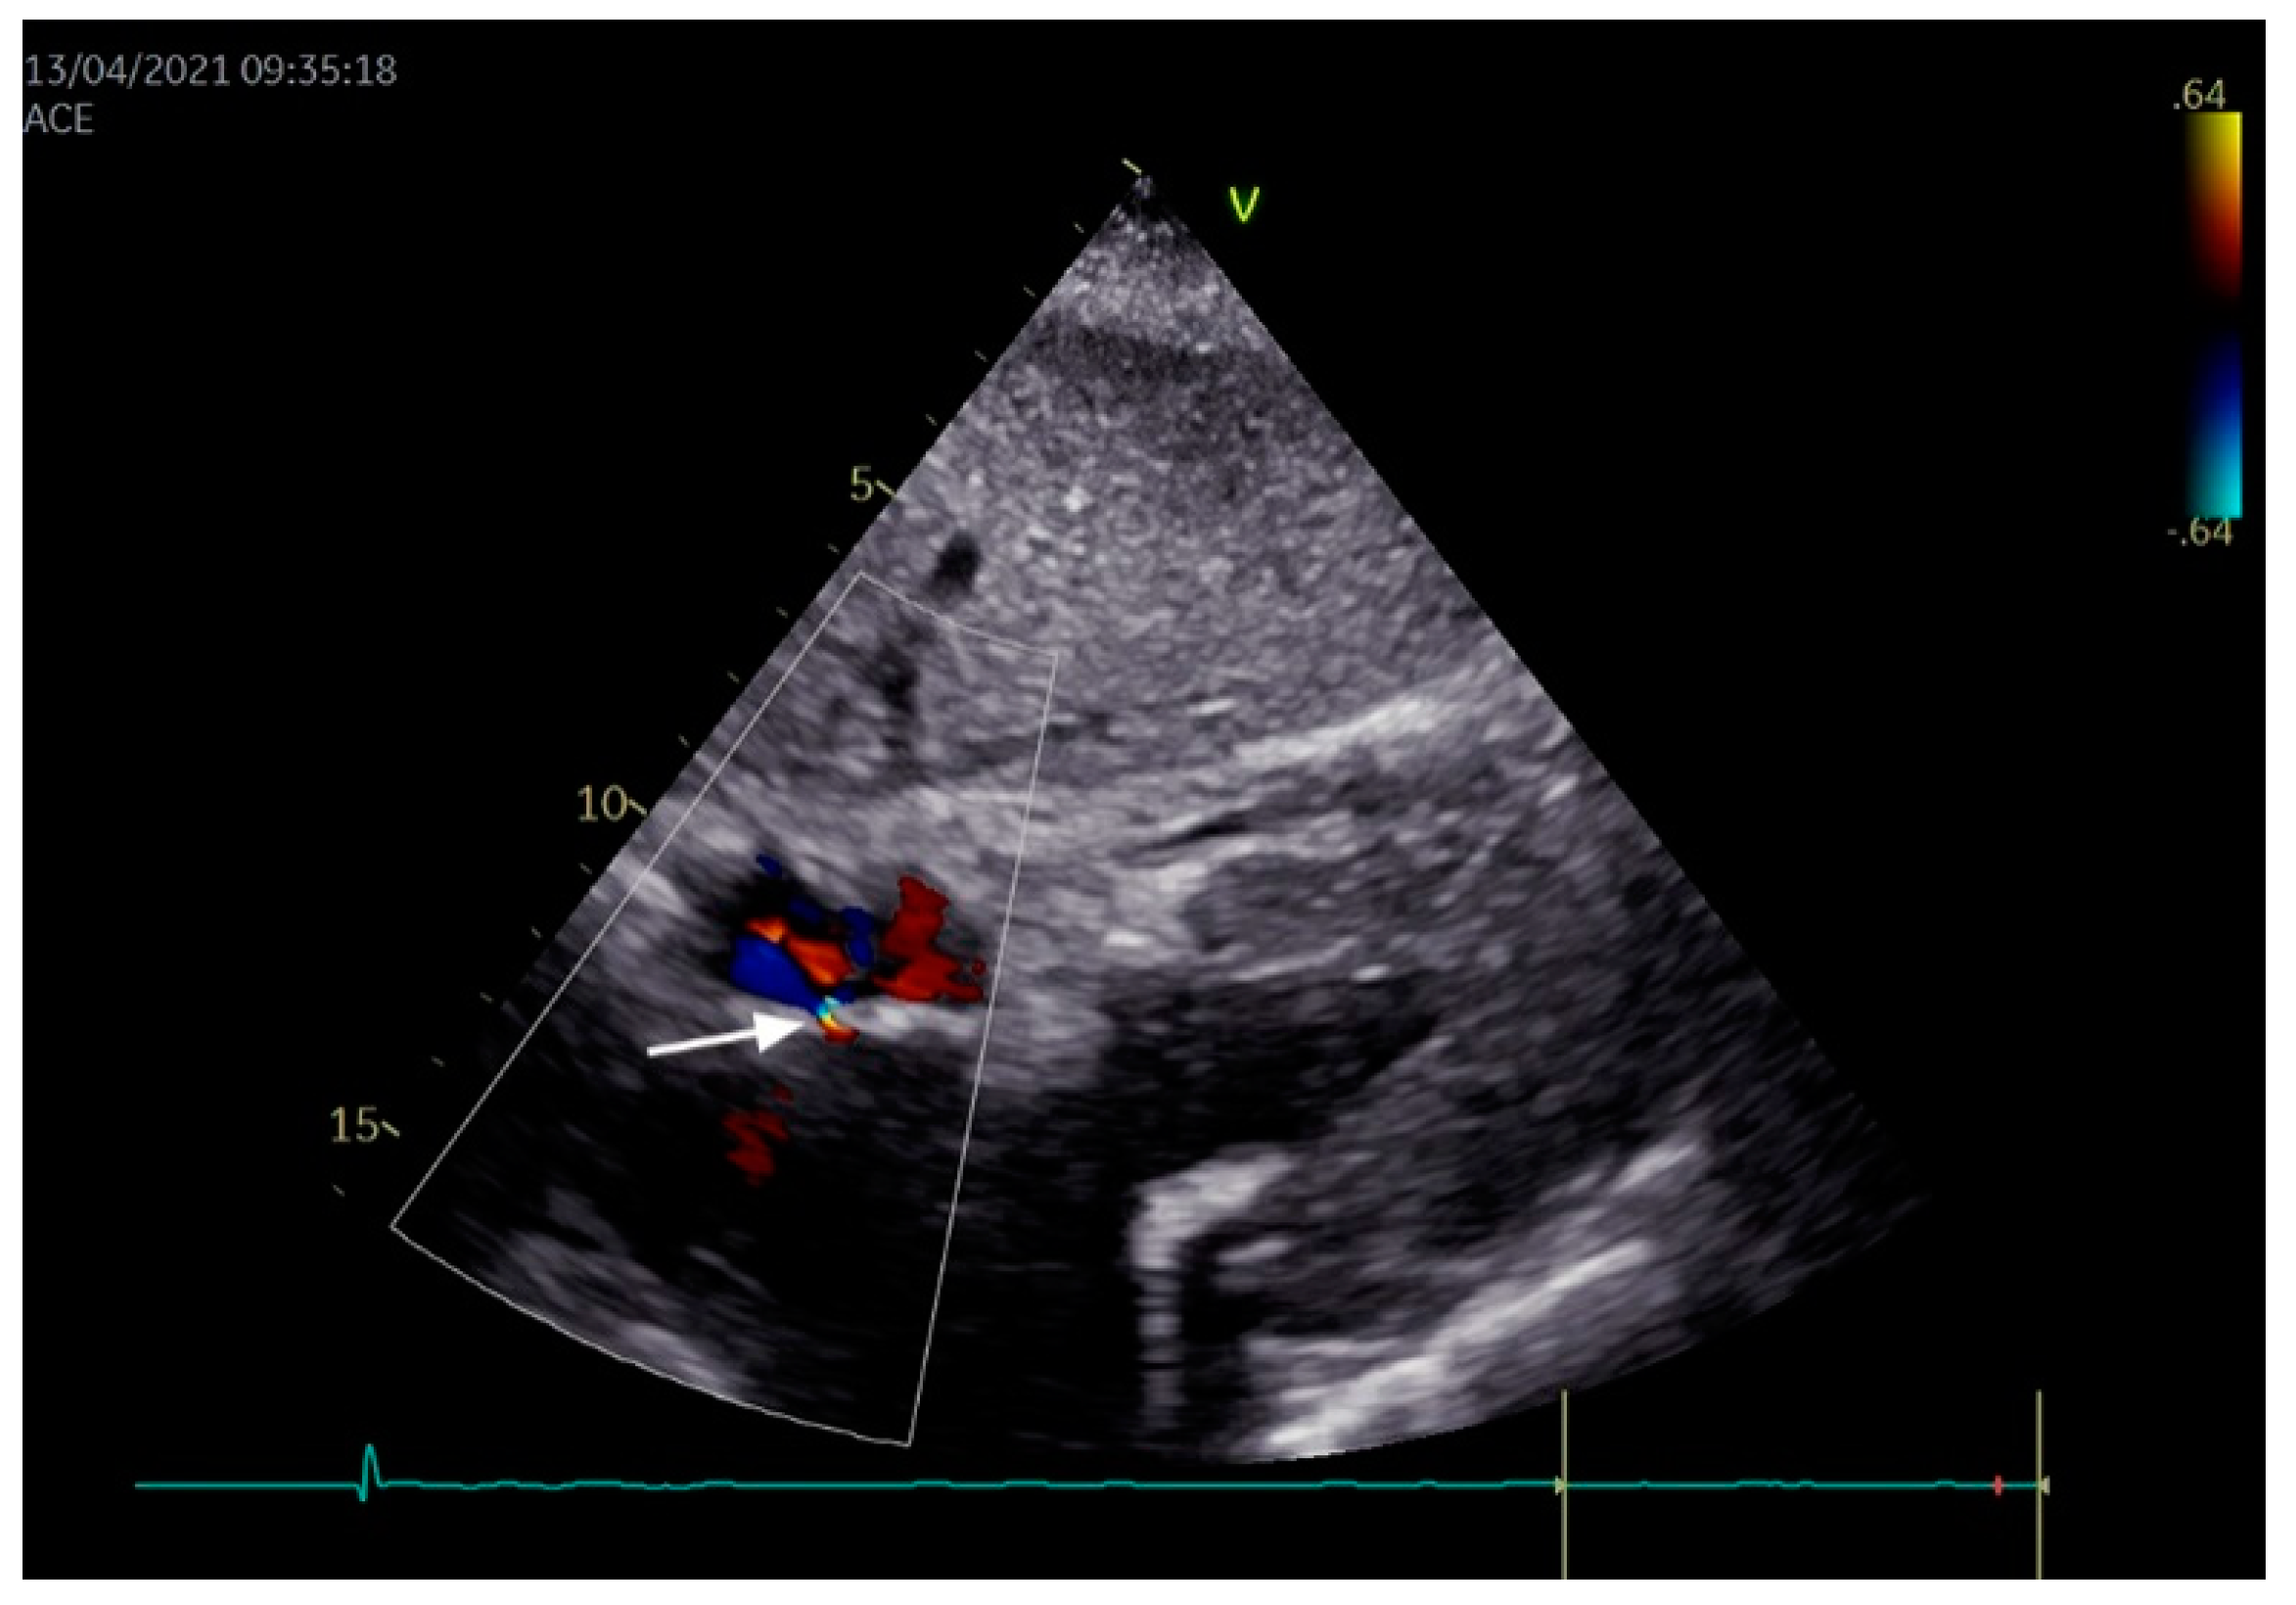

- Vitarelli, A. Patent foramen ovale: Pivotal role of transesophageal echocardiography in the indications for closure, assessment of varying anatomies and post-procedure follow-up. Ultrasound Med. Biol. 2019, 45, 1882–1895. [Google Scholar] [CrossRef]